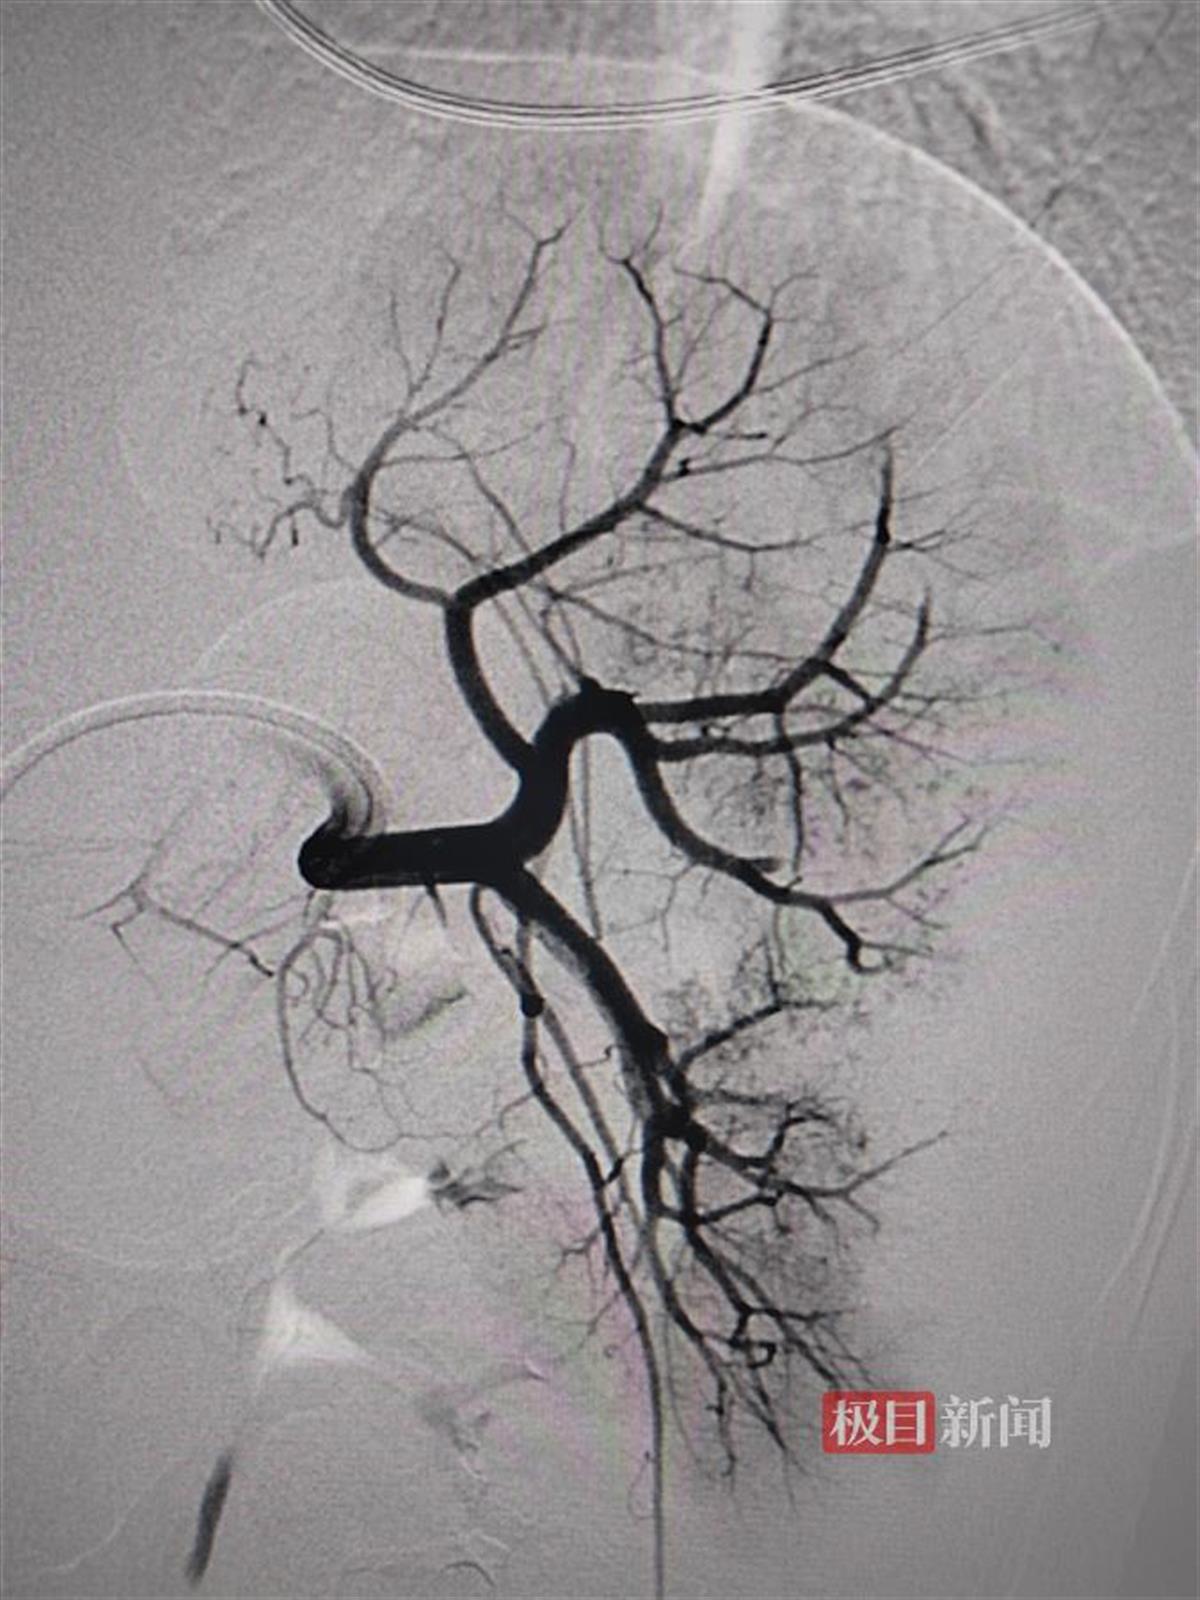

介入栓塞后的动脉造影

当日清晨,康康被推入手术室。术中,介入放射科主任刘新献、郭严延医生从孩子的右侧股动脉穿刺,将造影导管送到脾动脉主干,在造影剂的帮助下“锁定”出血的分支动脉,随后将微导管置入、实施栓塞,成功帮康康止血保脾。